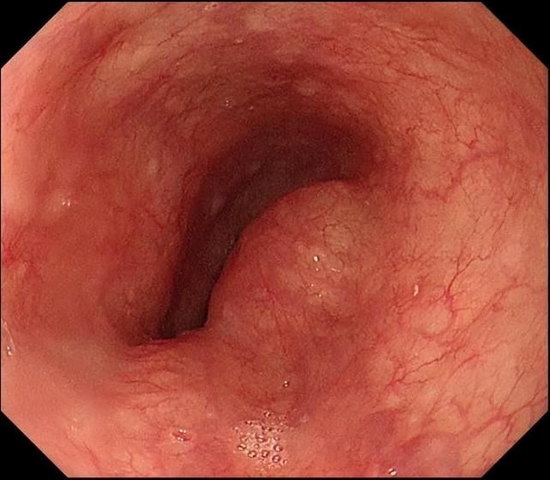

60岁的王女士这一年来间断出现吞咽不适、吞咽不流畅感等症状,于是来到西安市红会医院就诊。消化内科医生接诊后,仔细询问病史,并为患者立刻进行胃镜检查。

胃镜下可见食管中段隆起

检查中发现食管隆起性病变,考虑来源于管壁深层。为进一步明确诊断,消化内科韩霜主任为患者实施了超声胃镜检查。结果提示为固有肌层肿瘤,考虑平滑肌瘤的可能。